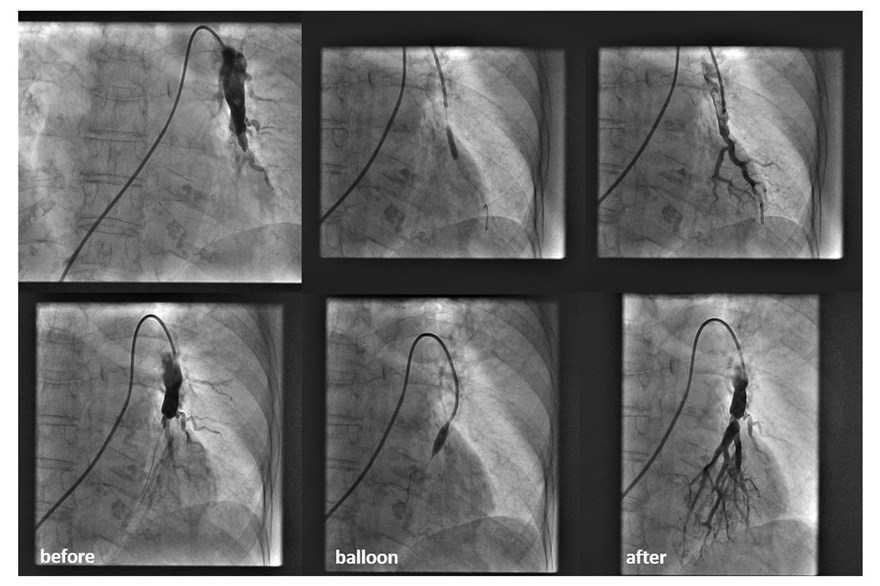

The first balloon pulmonary angioplasty (BPA) procedures for patients with chronic thromboembolic pulmonary hypertension (CTEPH) in Croatia have been successfully carried out at the Clinical Hospital Centre (KBC) Split.

Balloon pulmonary angioplasty, a less invasive alternative for non-surgical candidates, involves opening narrowed or blocked pulmonary arteries using a catheter and balloon, improving blood flow and reducing pulmonary pressure.